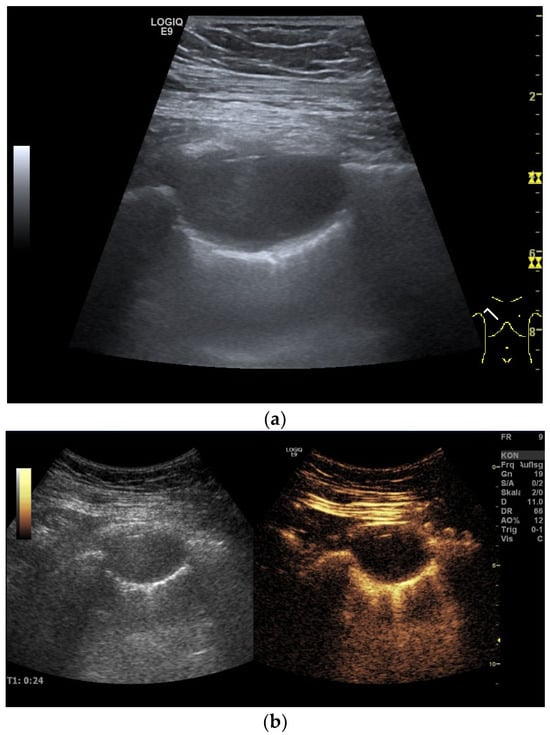

| Empyema | Hypoechoic thickened pleura, internal echos in the pleural effusion, hypoechoic pus, hyperechoic gas reflexes, fibrin strands, and chambering. In the phase of organization, thickened pleura, chambering of the pleural space. |

| Empyema necessitans | Exceeds the parietal pleura and infiltrates the surrounding soft tissue and chest wall muscles. |